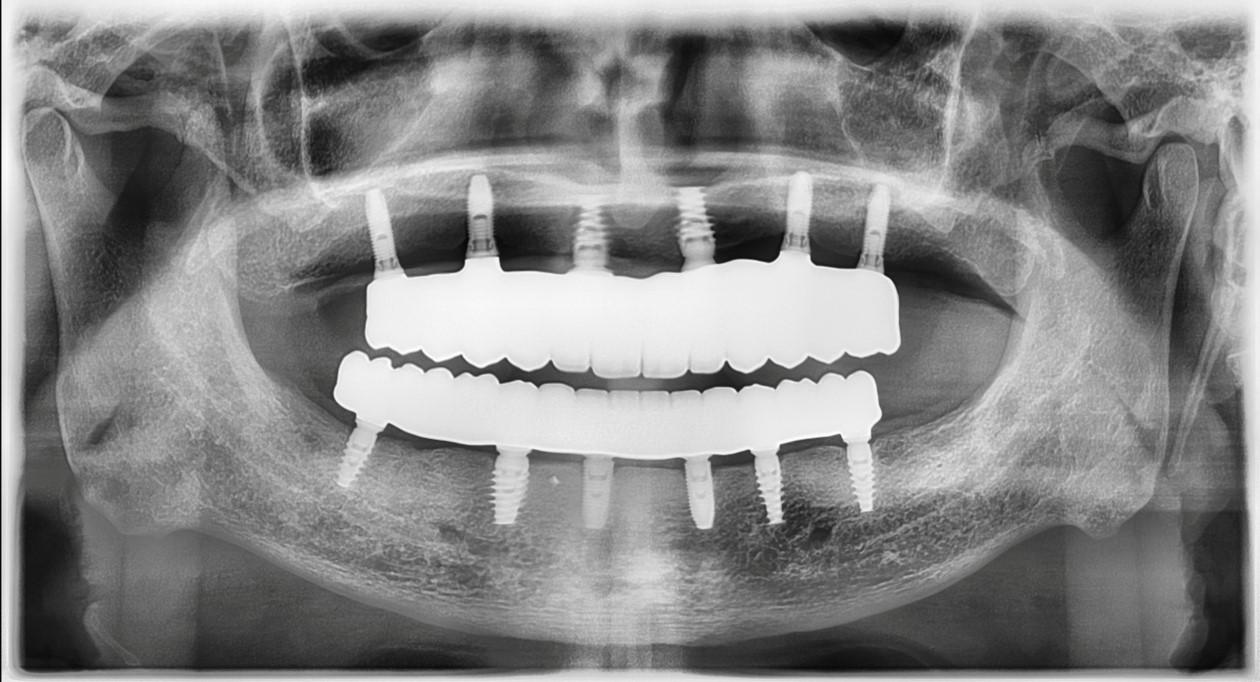

The revolutionary All-on-X (AOX) model-less workflow has become a reality through seamless integration of state-of-the-art technologies: interactive implant planning software, guided surgery systems, intraoral scanning (IOS), advanced 3D printing, and photogrammetry. Our innovative CAD-CAM protocols dramatically streamline the treatment process, reducing appointment frequency, chair time, and prosthetic delivery intervals. We've pioneered multiple digital workflows that ensure precise implant position recording and bite capture for full-arch implant rehabilitation.

The latest breakthroughs in 3D printing technology and materials enable same-day provisional restoration with unprecedented predictability. Clinicians can now consistently produce highly accurate temporaries that achieve perfect fit on multi-unit abutments (MUAs), whether using freehand or guided surgical approaches.